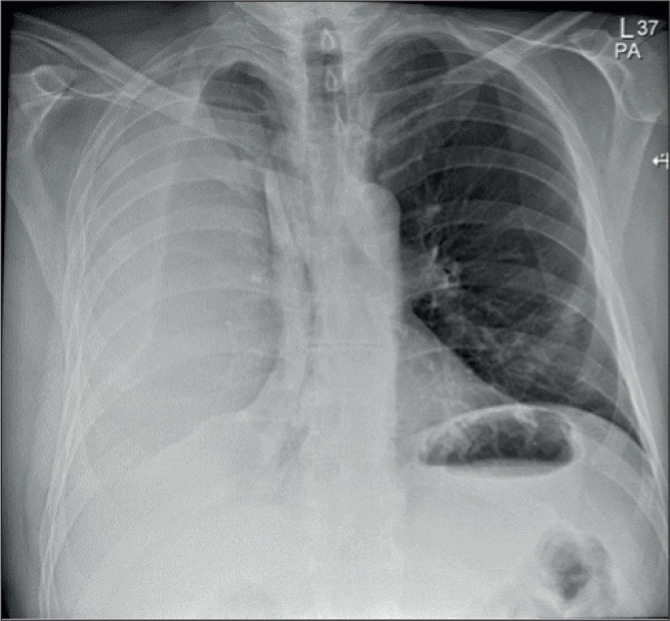

Extrapleural Haematoma following Percutaneous Coronary Intervention.

Abstract Image